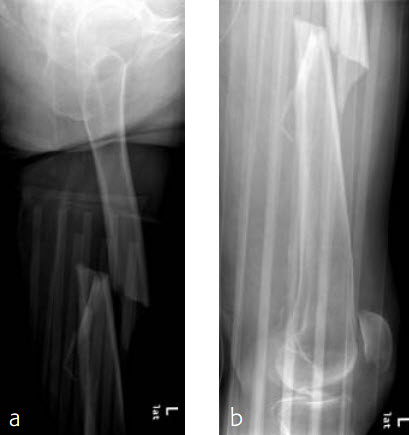

Case 2: Left femur fracture

A 70-year-old female patient suffered an AO 32-B3 fracture of the left femur (Figs 3 and 4). Fixation with the FRNA for a tip of the trochanter entry point (nail diameter 10 mm; nail length 400 mm; reaming to 12 mm) in standard interlocking mode (Figs 5 and 6). Proximal locking with antegrade and transverse dynamic locking positions. Distal locking with two lateral to medial locking screws in static locking position.